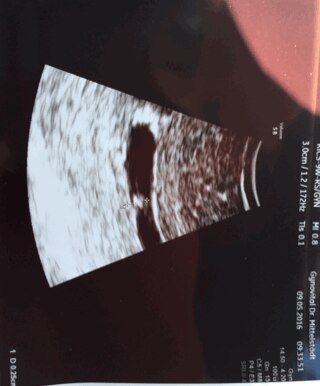

Hallo Mädels ich war heut beim Arzt 5+3 Alles ok Herzchen schlägt Nun meine Frage die fruchthöhle ist so Bananen förmig der Arzt sagte dazu nix ist das ok ? Lg

Bild zu Fruchthöhle - Schwanger - wer noch? Rund um die Schwangerschaft

Das ist doch sicherlich die Gebärmutter, nicht die Fruchthöhle. Die Fruchthöhle ist evtl. das Ding in der Mitte. Kann ich nicht sagen, das Bild ist auf meinem Tab zu klein. LG Lilly

Der Krümel wächst, das Herzchen schlägt. Da spielt die Form der Fruchthöhle keine Rolle. Außerdem kann sich das Bild durch den US ganz schön verziehen, wenn er sie iwi blöd erwischt hat. LG

Meine hatte in der 6. Woche auch eine ganz seltsame längliche Form. War alles ok.